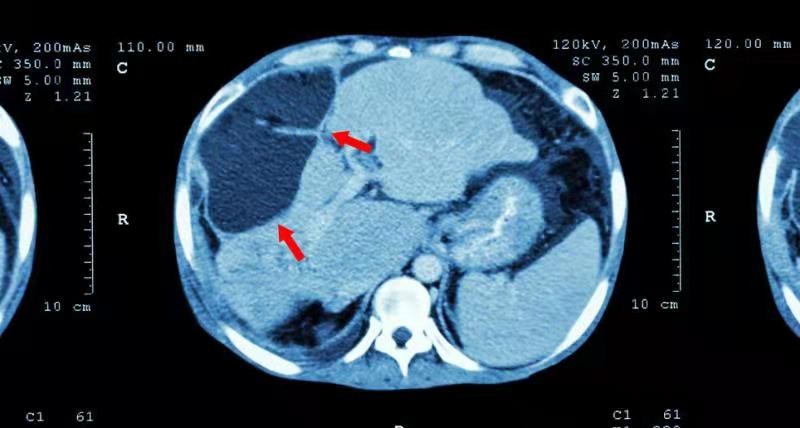

在醒来之后 , 已经在医院里了 , 是路人看到之后拨打了120 , 送往了医院 , 检查过后 , 发现其甲胎蛋白含量高达560 , 被确诊为肝癌 , 医生告诉他已通知家属 。

然而对于这种发霉的生姜 , 即使里面看着完好 , 其中也会布满霉菌 , 可能会含有黄曲霉素和黄樟素这类致癌物质 , 经常吃 , 由于摄入量太大 , 会影响到肝脏健康 , 肝功能发生紊乱情况 , 加上毒素在肝脏内的不断累积 , 最终引发肝癌 。